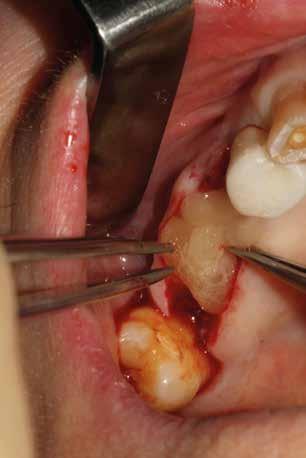

Estrazione di 3 elementi dentari complicata da frattura coronale di 2.4 e presenza di 2 corone protesiche unite su denti pluriradicolati. L’approccio deve prevedere la rimozione delle corone protesiche e la separazione delle radici, semplificando le manovre di estrazione e consentendo di risparmiare i tessuti molli pericoronali e prevenire la frattura

Il rispetto dei tessuti molli consente di ridurre i tempi di guarigione, sebbene a siti più ampi corrisponda un tempo di ripristino o maggiore. Il mantenimento delle corticali vestibolari, palatine e l’assenza di alveolite post-estrattiva riducono l’atrofia ossea.

FIG. 2 FIGG. 5,6: FIG. 5 FIG. 6 FIGG. 3,4: delle corticali ossee più sottili. FIG. 3 FIG. 4